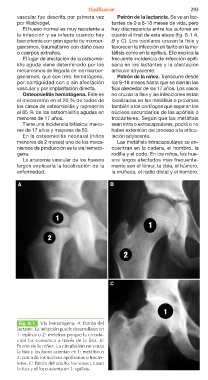

vascular fue descrita por primera vez Patrón de la lactancia. Se ve en lac-

por Waldvogel. tantes de 0 a 8-18 meses de vida, pero

hay discrepancia entre los autores en

El hueso normal es muy resistente a cuanto al final de esta etapa (fig. 8-1 A,

la infección y se infecta cuando hay B y C). Los capilares cruzan la fisis y

bacteriemia con gran aporte de microor- favorecen la infección en tanto en la me-

ganismos, traumatismo con daño óseo táfisis como en la epífisis. Ello explica la

o cuerpos extraños. frecuente incidencia de infección epifi-

saria en los lactantes y la afectación

El lugar de afectación de la osteomie- articular adyacente.

Fig. 8-1 Vía hematógena. A: Patrón del

lactante. La infección puede desarrollarse en

1: epífisis o 2: metáfisis porque la circula-

ción las comunica a través de la fisis. B:

Patrón de la niñez. La circulación no cruza

la fisis y los focos asientan en 1: metáfisis o

2: cerca de los núcleos apofisarios o trocán-

teres. C: Patrón del adulto, los vasos cruzan

la fisis y el foco asienta en 1: epífisis.